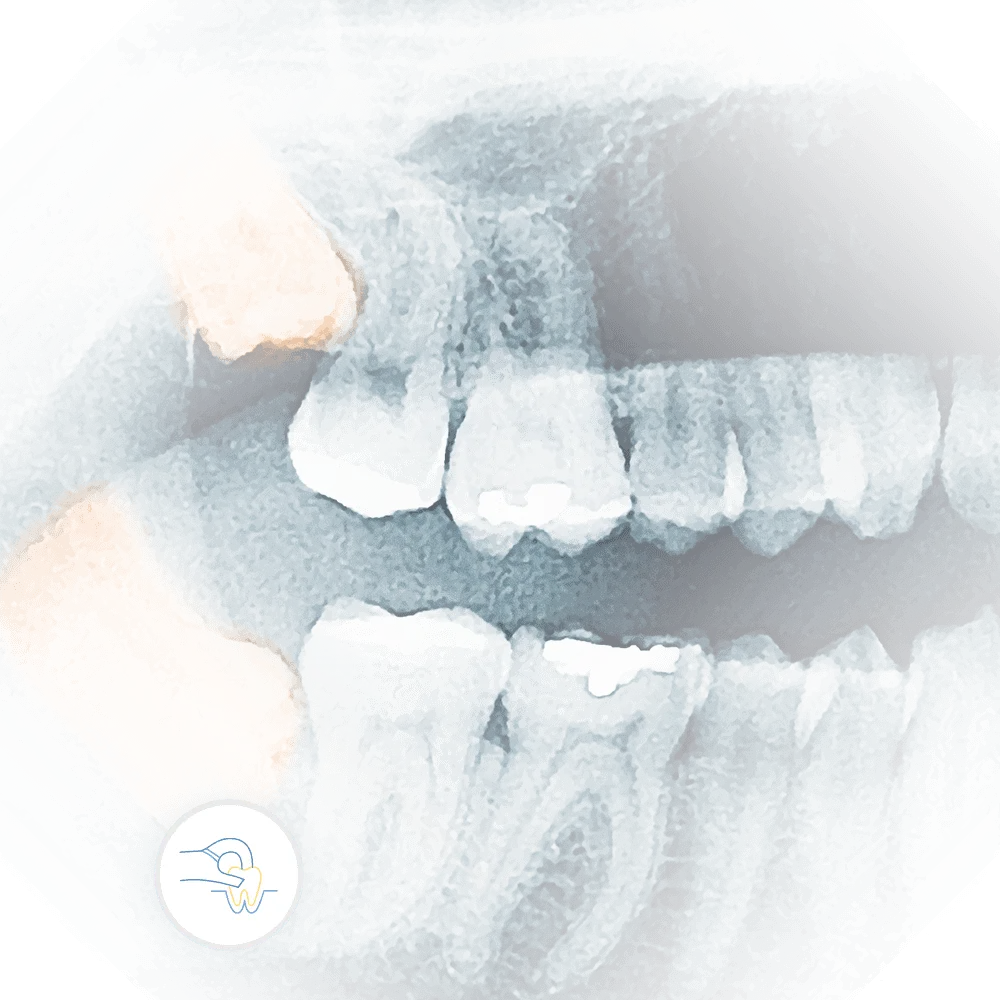

x-ray of impacted teeth requiring dental tooth extraction

Tooth Extraction

When a tooth needs to be removed, it's crucial to have a skilled and caring team. At Vartanian Dental Group, we perform tooth extractions with precision and minimal discomfort. Our priority is to ensure a smooth, pain-free experience, helping you on your way to optimal oral health.